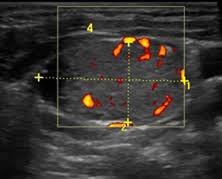

Colon Cancer Ultrasound Radiology Case Radiopaedia Org from prod-images-static.radiopaedia.org To see whether the cancer has spread, some or all of the lymph nodes are removed and checked for cancerous cells. We prospectively studied 19 patients referred to the institut gustave. It can be used with a fine needle aspiration test or core biopsy test to accurately direct the tip of the needle into the lump. If this lump is of concern then a biopsy would be the next step. They deliver blood from your heart to your brain. Head and neck cancers include cancers in: However, an ultrasound can tell if a lymph node has an abnormal architecture possibly because it is infiltrated by tumor. Sonography, when performed by an experienced examiner, can be used for evaluation of many pathologies in the head and neck area.

While it can't diagnose cancer, it can detect the abnormal tissues that may possibly be cancerous. Ultrasound is often one of the first line tests in the detection of cancer. For neck or thyroid mass see ent. Lymph nodes are part of the lymphatic system, which helps to protect us from infection and disease. Some of the indications for thyroid or neck ultrasound are thyroid nodules, goiter, thyroid cancer and other neck masses. Ultrasound imaging is a noninvasive medical test that helps physicians diagnose and treat medical conditions. Part of the throat (cancers of the oropharynx and tonsils, nasopharynx and hypopharynx) the nose or sinuses (nasal and sinus cancer) the salivary glands. Ultrasound guidance is used to perform thyroid biopsies and improves the diagnostic accuracy of fine needle biopsy. Sonography has an accuracy rate of about … Fna might also be used in patients whose cancer has been treated by surgery and/or radiation therapy , to help find out if a neck mass in the treated area is scar tissue or if it's a return (recurrence) of the cancer. If the person has a lump in the neck, an fna can show if the mass is from cancer spread. It can be used with a fine needle aspiration test or core biopsy test to accurately direct the tip of the needle into the lump. It can detect abnormal tissues, growths, and cysts and give a suspicion of cancer based on how those images look.